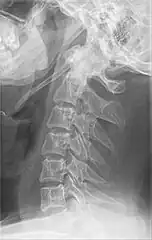

| Anteroposterior and lateral radiographs of cervical spine showing ossification of the stylohyoid ligament on both sides | |

Radiograph, lateral view showing elongated stylohyoid process and stylohyoid ligament ossification -

Radiograph, lateral view showing joint-like formation in ossified stylohyoid ligament -